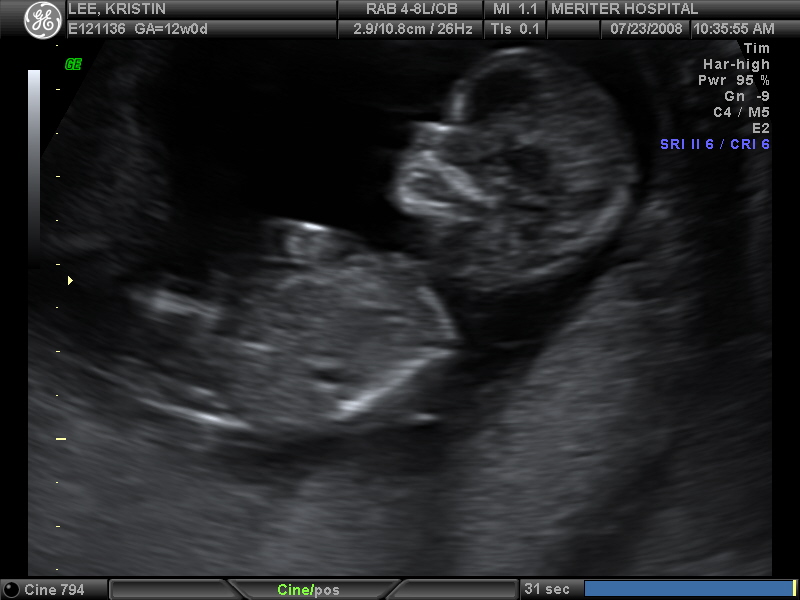

Ultrasound